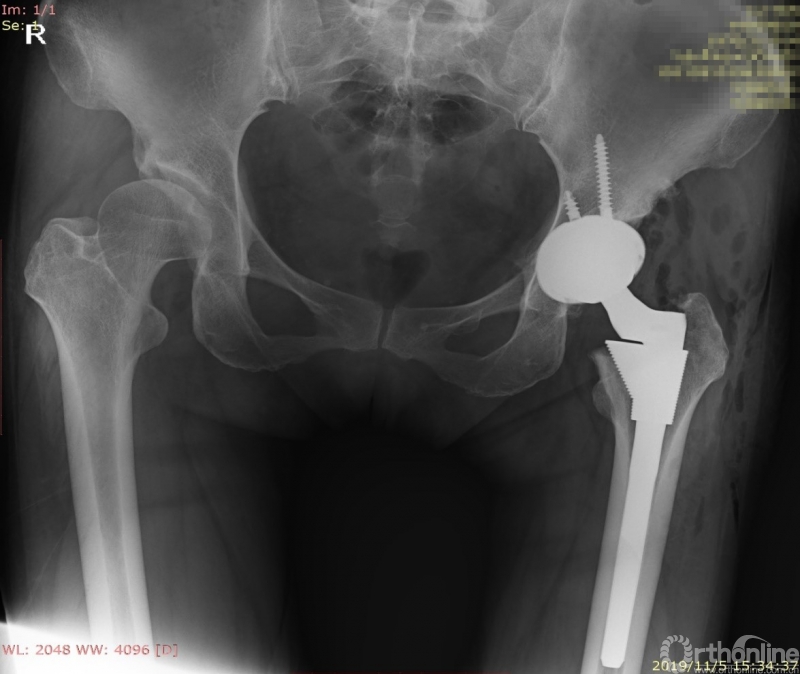

患者术后X线片

根据规划结果,术前模拟得到术后X线片,并精确显示出髋臼杯、股骨柄假体在原有CT图像上的轮廓位置,以供术者进行参考。由于术前准备充分,手术过程开展顺利,仅60分钟即完成了手术,术后X线与规划一致,患者功能恢复良好,术后第二天即可下地行走。